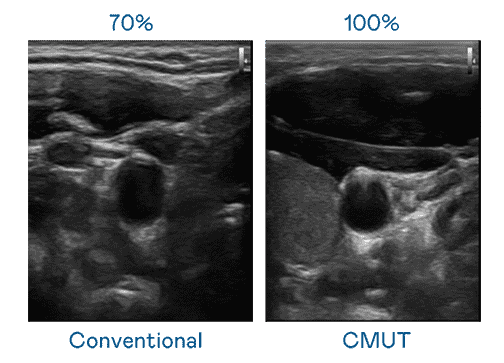

CMUT 技术是一种用电容式微机电元件来产生超音波讯号的技术。。。。与传统 PZT 压电式技术相比,,,,CMUT 频宽增加 30%,,更宽频的超音波讯号让影像解析度大幅提升,,,是实现高影像品质医疗超音波扫描、、促进精准医疗发展的关键技术。。。

超音波影像的解析度高低,,,首先取决于探头能发出的讯号频宽。。。。巨星国际 CMUT 可提供高清晰的超音波讯号,,,提供高频宽、、、、高灵敏度、、、影像纹理细节更高的超音波影像,,协助医护人员缩短影像判读时间及利用精准的医疗影像进行诊断。。。